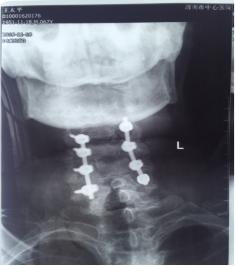

术 后

11月13日行手术治疗,后前路联合手术。先行颈后路切开,颈3-6椎体侧块螺钉固定,再行前路颈4.5间盘以及颈前脓液清理,椎间隙植骨融合术。术中见颈4.5椎间隙前缘被一直径1.5㎝肿物包裹,打开后,可见其内少许米汤样脓性液,肿块壁为脓性物。间盘内充填相同物,上、下缘软骨板漂浮,翘起,上下椎体相邻面骨质酥脆,同时后缘有大量不良增生物,骨钩分离后,可见自颈5椎体后缘,流出同样的米汤样脓液。彻底清理脓性液,充分刮除椎体不良骨质。大量生理盐水冲洗,取三面皮质髂骨块置于椎间隙,敲紧。术后前侧放引流管于脓腔间隙。术后留置3.5天。术中留取的脓液细菌培养仍为阴性,刮出的椎间盘及囊壁病检结果显示为化脓性炎表现。术后继续抗生素治疗,患者体温正常,四肢肌力改善明显,下肢肌力术后第2天恢复至2级。上肢肌力4级弱。躯干部位感觉平面下降至乳头以远,大小便功能改善不明显。